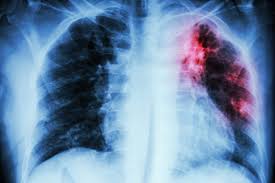

Lung cancer is often divided into two types: Lung cancer is the leading cause of cancer death worldwide, with approx. Tuberculosis (tb) is caused by bacteria (mycobacterium tuberculosis) that most often affect the lungs. Tuberculosis (tb) is a contagious infection that usually attacks your lungs. Lung cancer is most often discovered by mistake if it is detected in the early stages.

Since mycobacterium tuberculosis (mtb) is an intracellular organism, bacterial dna could integrate to bronchial epithelial cells inducing neoplastic transformation. 90% of cases being attributable to smoking. Lung cancers are generally divided into 2 main categories: Is it possible for the doctor to mistake a possible lung cancer for tb? Can lung cancer be found early? Even when lung cancer does cause symptoms, many people may mistake them for other problems, such as an. When lung cancer is suspected, a physician will perform a thorough history and physical exam. The occurrence of pulmonary tuberculosis (ptb) and lung cancer as comorbidities has been extensively discussed in many studies. The incidence of both conditions remains high in many developing countries, especially in east asia. In the past, it was well known that lung cancer is a specific epidemiological successor of ptb and that lung cancer often develops in scars caused by ptb. Living with advanced breast cancer. Pulmonary tuberculosis and lung cancer. Lung cancer is most often discovered by mistake if it is detected in the early stages.

Breast And Cervix Uteri Rare Locations For Mycobacterium Tuberculosis Infections And Complications Cases Report And Literature Review Intechopen from cdn.intechopen.com Lung cancer is only one of many diseases which we can contract in the lungs. Even if a mass is found, it may not be cancerous, and further studies are required to confirm its status. Symptoms of tuberculosis and lung cancer are overlapping and it is difficult to differentiate without the histopathological report. When people with lung tb cough, sneeze or spit, they propel the tb germs into the air. This is one reason that it is among the most deadly of cancer groups. Pulmonary tuberculosis (tb) may coexist with lung cancer and share some similarities with these conditions. Tb and lung cancer have been confused and misdiagnosed for centuries 2. 90% of cases being attributable to smoking.

When lung cancer is suspected, a physician will perform a thorough history and physical exam. Pulmonary tuberculosis (tb) may coexist with lung cancer and share some similarities with these conditions. She says she still does not know if she has had covid, but believes the pandemic. When people with lung tb cough, sneeze or spit, they propel the tb germs into the air. Tuberculosis (tb) is caused by bacteria (mycobacterium tuberculosis) that most often affect the lungs. Tb and lung cancer have been confused and misdiagnosed for centuries 2. Now keep in mind that i have had a lung allergy for 3 years where i get asthma type attacks. The occurrence of pulmonary tuberculosis (ptb) and lung cancer as comorbidities has been extensively discussed in many studies. Patients with lung cancer are often misdiagnosed as pulmonary tuberculosis leading to delay in the correct diagnosis as well as exposure to inappropriate. Tuberculosis (tb) is a contagious infection that usually attacks your lungs. Tuberculosis germs don't thrive on surfaces. Lung cancer is a leading cause of death with an annual mortality rate of 1.59 million people, accounting for 19.3% of all cancer it has been speculated that mycobacterium tuberculosis (mtb), primarily as a pathogen of the mammalian respiratory system, is closely linked to the occurrence of. Lung cancer, also known as lung carcinoma, is a malignant lung tumor characterized by uncontrolled cell growth in tissues of the lung.

Possible causes, signs and symptoms, standard treatment options and means of care and support. Tb is spread from person to person through the air. When people with lung tb cough, sneeze or spit, they propel the tb germs into the air. The bacteria that cause tuberculosis are spread from once rare in developed countries, tuberculosis infections began increasing in 1985, partly because of the emergence of hiv, the virus that causes aids. Interestingly so, tuberculosis has been known to mimic lung cancer due to its presentation in the form of pulmonary infiltrates and mediastinal lymphadenopathy however, in the reported cases where pulmonary tuberculosis was mistaken for pulmonary malignancy, a number of different, costly. Difference between lung cancer and tuberculosis. Tuberculosis (tb) and lung cancer are important global health threats, each accounting for 1.6 million deaths yearly. Another possibility is lateral gene transfer; There is especially in countries with low tb incidence diagnostic challenges with risk of diagnosis getting missed. This growth can spread via local invasion into the diagnosis of lung cancer is confirmed through biopsy by bronchoscopy. Helen has now had treatment for her lung cancer and is recovering well. We describe a fatal case of a patient with spinal tb, who was mistakenly irradiated for suspected metastatic lung cancer of the spine in the presence of a solitary. Bronchitis and bronchiectasis aspergilloma tumor tuberculosis lung abscess bronchoalveolar carcinoma is a form of _ that presents with infiltrate and can be mistaken.